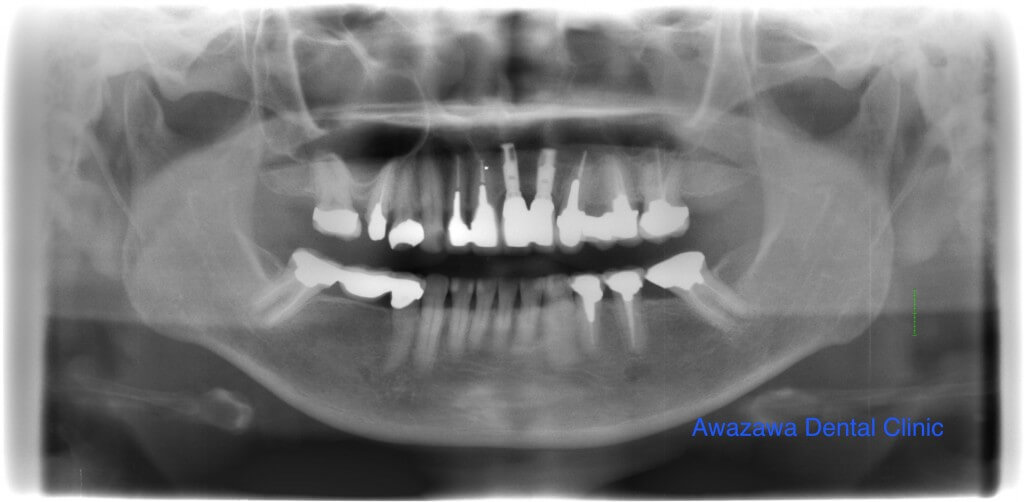

重度の歯周病と虫歯により咬合が崩壊してしまった症例です。上下の顎の前後的な位置に著しい不調和が認められ下顎の前歯が上顎の歯肉に咬み込んでいらっしゃいました。上下全額にわたりインプラントによる咬合再建を行いました。治療後の写真は治療終了3年経過後の状態です。(ご本人の希望で歯にステインによる着色を施してあります。)